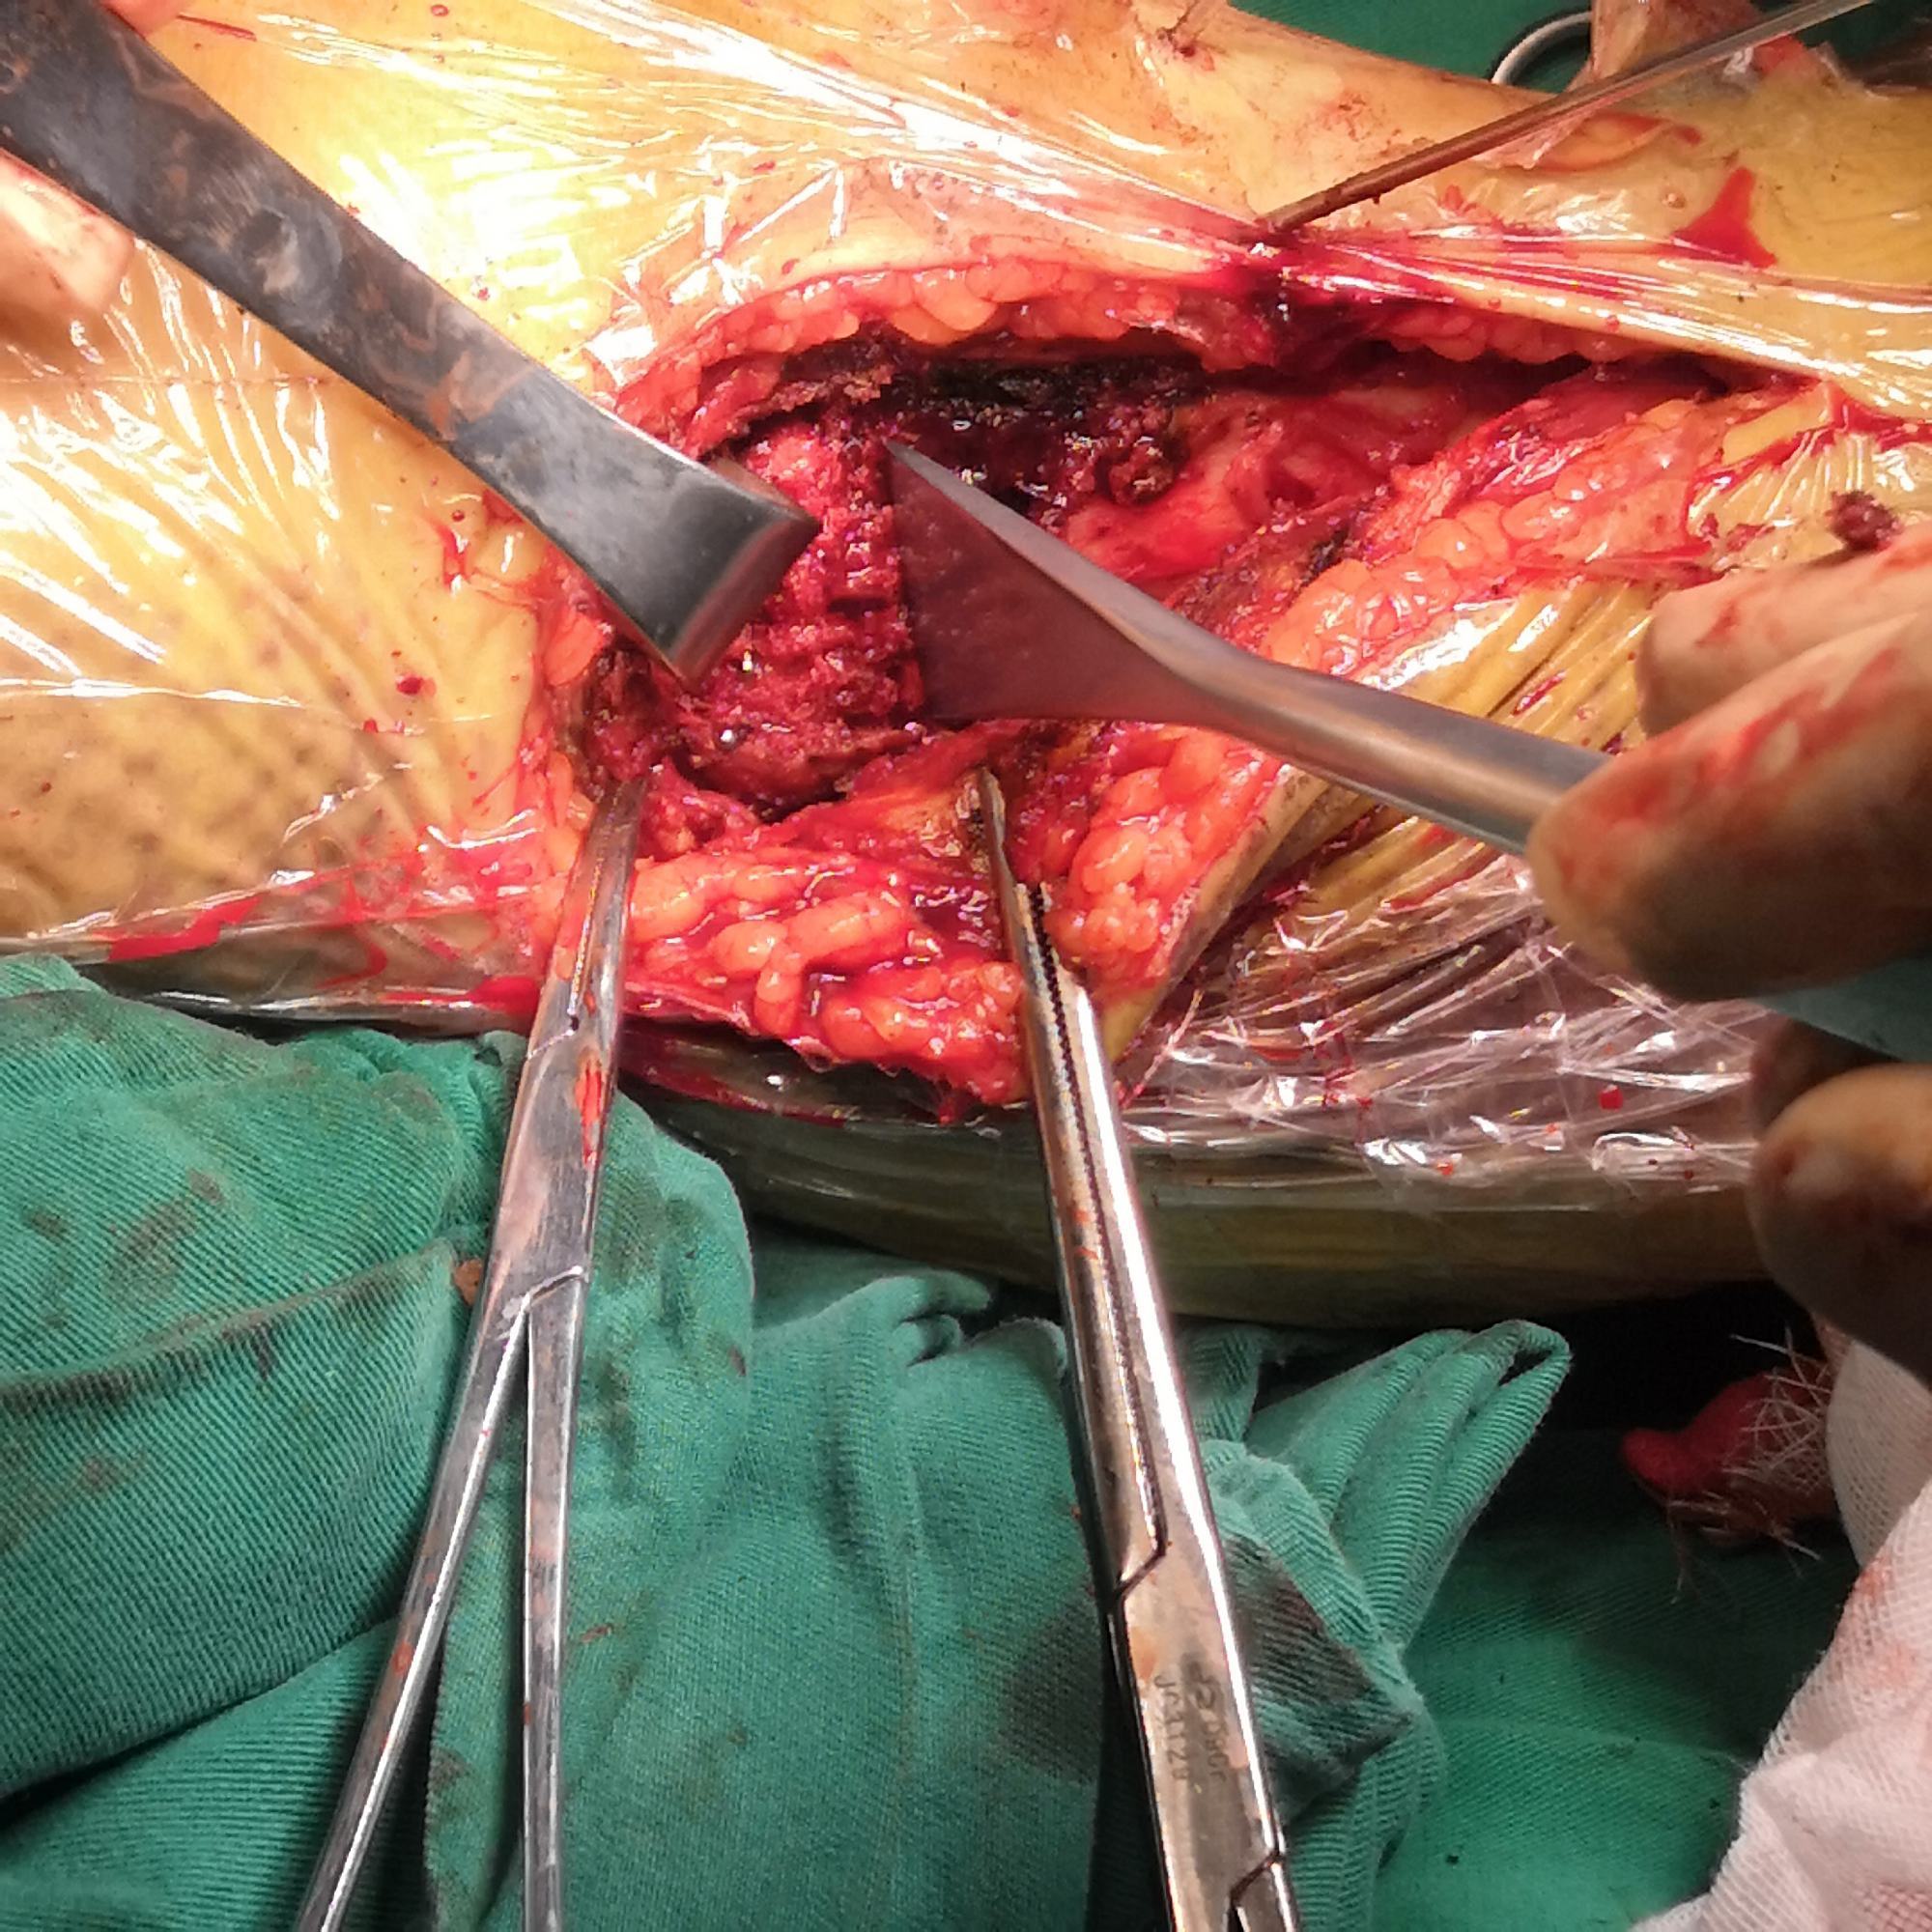

切开探查

进一步复位、植骨内固定